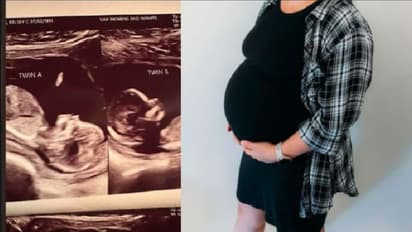

ನ್ಯೂಯಾರ್ಕ್: ಅಮೆರಿಕಾದ ಅಲ್ಬಾಮಾದ ಮಹಿಳೆಯೊಬ್ಬರೂ ಎರಡು ಗರ್ಭಕೋಶಗಳನ್ನು ಹೊಂದಿದ್ದು, ಎರಡರಲ್ಲೂ ಕಂದನನ್ನು ಹೊಂದಿದ್ದು, ವೈದ್ಯಕೀಯ ಅಚ್ಚರಿಗೆ ಕಾರಣರಾಗಿದ್ದಾರೆ. ಈಗಿನ ಕಾಲದಲ್ಲಿ ಗರ್ಭಕೋಶ ಸುಸ್ಥಿರವಾಗಿರುವುದೇ ಕಷ್ಟದ ವಿಚಾರ ಪ್ರಪಂಚದಾದ್ಯಂತ ಲಕ್ಷಾಂತರ ಹೆಣ್ಣು ಮಕ್ಕಳು ಗರ್ಭಕೋಶದ ಕ್ಯಾನ್ಸರ್ನಿಂದ ಬಳಲುತ್ತಿದ್ದಾರೆ. ಇರುವ ಒಂದು ಗರ್ಭವನ್ನು ಉಳಿಸಿಕೊಳ್ಳುವುದಕ್ಕಾಗಿ ಅನೇಕರು ಕಷ್ಟಪಡುತ್ತಿದ್ದಾರೆ. ಹೀಗಿರುವಾಗ ಇಲ್ಲೊಬ್ಬರು ಮಹಿಳೆ ಎರಡೆರಡು ಗರ್ಭಕೋಶವನ್ನು ಹೊಂದಿದ್ದು ಇದರ ಜೊತೆಗೆ ಎರಡರಲ್ಲೂ ಮಗುವನ್ನು ಹೊಂದುವ ಮೂಲಕ ಸ್ವತಃ ಅವರೇ ಅಚ್ಚರಿಗೆ ಕಾರಣರಾಗಿದ್ದಾರೆ.

ಈಗ ಎರಡು ಮಕ್ಕಳಿಗೆ ಗರ್ಭವತಿಯಾಗಿರುವ ಮಹಿಳೆಗೆ ಈಗಾಗಲೇ 7 , 4 ಹಾಗೂ 2 ವರ್ಷ ಪ್ರಾಯದ ಮೂರು ಮಕ್ಕಳಿದ್ದು, ವೈದ್ಯರ ಬಾಯಿಯಿಂದ ಬಂದ ಈ ಎರಡು ಗರ್ಭಕೋಶದ ಮಾತು ಕೇಳಿ ಅಚ್ಚರಿಯ ಜೊತೆ ನಂಬಲಾಗದಂತಹ ಸ್ಥಿತಿಯಲ್ಲಿದ್ದಾರೆ. 32 ವರ್ಷದ ಕೆಲ್ಸಿ ಹ್ಯಾಚರ್ ಎಂಬುವವರೇ ಈ ರೀತಿ ವಿರಳವಾದ ಎರಡು ಗರ್ಭಕೋಶಗಳನ್ನು ಹೊಂದಿರುವ ಮಹಿಳೆ.

ಈ ಸ್ಥಿತಿಯನ್ನು ಯುಟೆರಿನ್ ಡಿಡೆಲ್ಫಿಸ್ ಎಂದು ಕರೆಯಲಾಗುತ್ತದೆ. ಈ ಸ್ಥಿತಿಯಲ್ಲಿರುವ ಕೆಲ್ಸಿ ಅವರು ಇಬ್ಬರು ಅವಳಿ ಮಕ್ಕಳಿಗೆ ಜನ್ಮ ನೀಡಲಿದ್ದು, ಅವರ ಒಂದೊಂದು ಗರ್ಭದಲ್ಲಿದ್ದು, ಒಂದೊಂದು ಮಗುವಿದೆ. ಈ ಅಚ್ಚರಿಯ ಪ್ರಕರಣವೂ ಇವರಿಗೆ 8ನೇ ವಾರದ ಅಲ್ಟ್ರಸೌಂಡ್ ಸ್ಕ್ಯಾನಿಂಗ್ ವೇಳೆ ಕಂಡು ಬಂದಿದ್ದು, ಇದು ಕೆಲ್ಸಿ ಹಾಗೂ ಆಕೆಯ ಪತಿ ಕ್ಯಾಲೆಬ್ ಇಬ್ಬರನ್ನು ಶಾಕ್ಗೊಳಗಾಗುವಂತೆ ಮಾಡಿತ್ತು. ಈಗಾಗಲೇ ಮೂರು ಮಕ್ಕಳ ಪೋಷಕರಾಗಿರುವ ಈ ದಂಪತಿ ವೈದ್ಯರ ಈ ಹೇಳಿಕೆಯನ್ನು ನಂಬಲು ಕಷ್ಟಪಡುತ್ತಿದ್ದರು. ಕೆಲ್ಸಿ ಅವರು ಕ್ರಿಸ್ಮಸ್ ದಿನ ಇಬ್ಬರು ಮಕ್ಕಳಿಗೆ ಜನ್ಮ ನೀಡಲಿದ್ದಾರೆ.